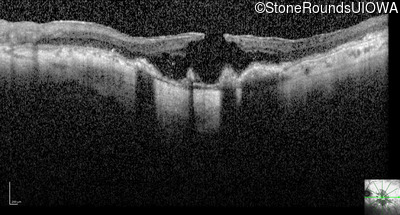

Optical Coherence Tomography - Left - Count Fingers 2'

Exemplar / OCT Stack

OCT Stack